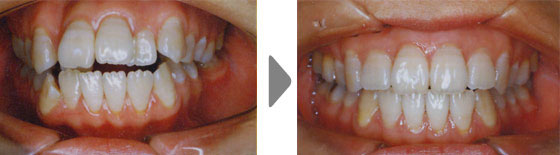

審美の改善

上顎前突(出っ歯)、下顎前突(受け口)や叢生(でこぼこの歯列)は笑った時の見た目はもちろん、口を閉じた顔貌の調和も乱れてしまいます。